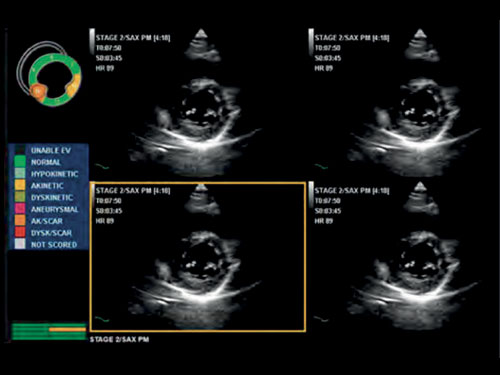

Stress echo: Kompletní balíček stress echa s flexibilními a přizpůsobitelnými protokoly pro získávání a kontrolu zobrazování, k dispozici také u LVO.